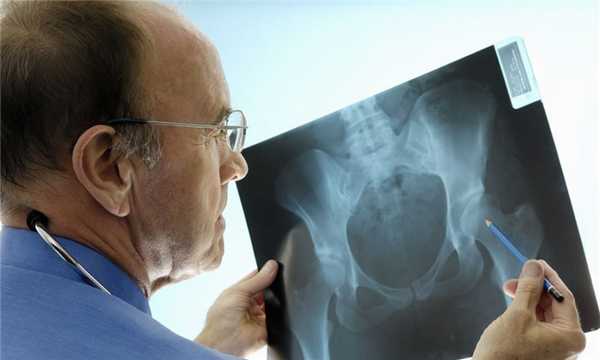

Как делают рентген тазобедренного сустава

Чтобы получить исчерпывающие сведения о состоянии пациента, ему делают обзорную рентгенограмму таза в прямой проекции. Проведение рентгенографии только одного сустава является ошибкой. Для полноценного анализа рентгенологу необходимо видеть снимки обоих ТБС. Часто выявить патологию ему помогает именно сравнение.

- Проведение исследования. Для получение обзорной рентгенограммы пациента укладывают на спину. Таз исследуемого не должен наклоняться и поворачиваться. Чтобы получить правильное отображение шеечно-диафизарного угла, рентгенолог разворачивает обе стопы больного кнутри на 15 градусов. Установив рентгеновскую трубку, он выходит из комнаты и делает снимок.

Рис 1. Укладка пациента при выполнении обзорной рентгенографии в прямой проекции.